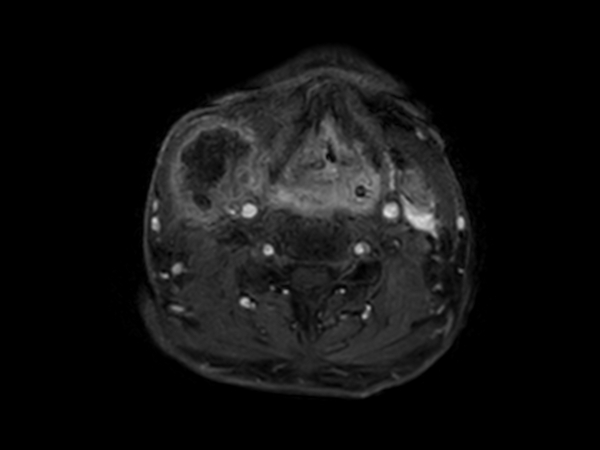

Axial STIR TSE